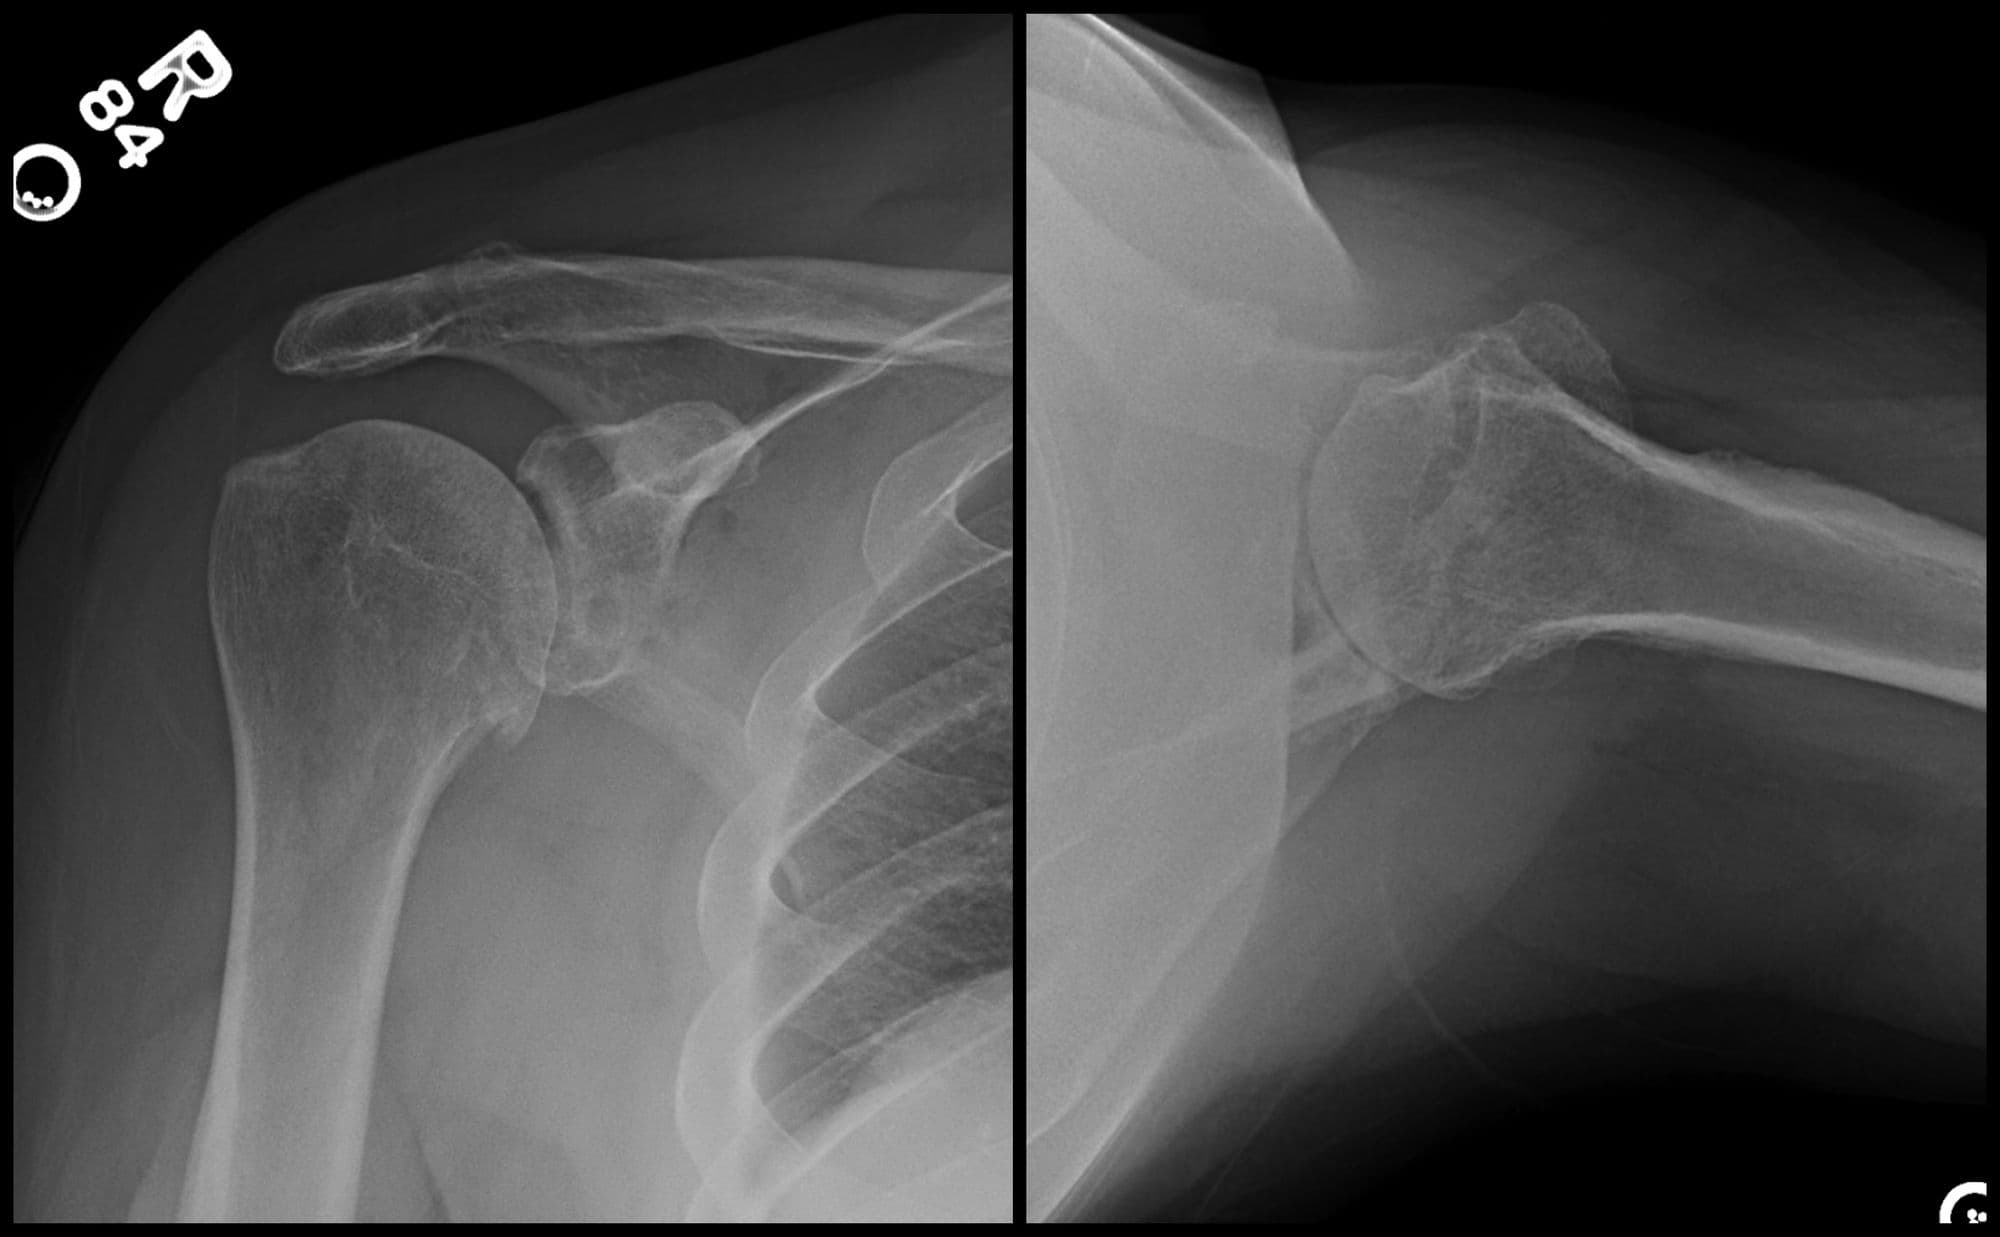

Glenoid Reconstruction with Allograft